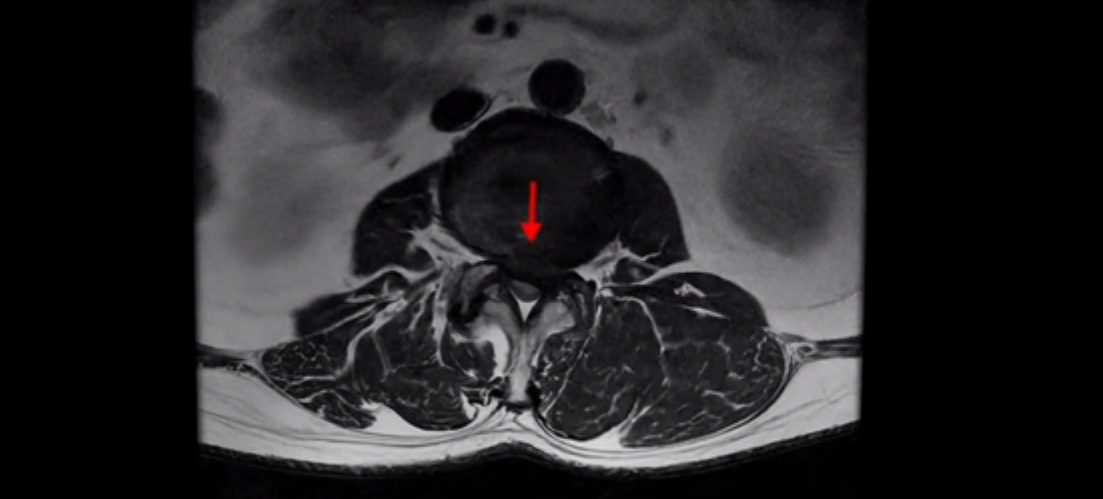

이 환자분은 고관절 쪽이 10년이 넘게 아팠고, 5년 전에는 갑자기 허벅지와 다리가 아파 못 걷게 돼서 허리 수술을 받습니다. 그리고 3년 후에 다시 재발합니다. 고관절 통증은 허리 수술 이후에도 좋아지지 않고 계속 아팠습니다. 수술하고 재발한 이후로 원래부터 아프던 고관절은 물론, 양쪽 엉덩이와 사타구니 및 허벅지가 다 아파서 잘 걷지도 못하고 또 앉거나 누워도 아파서 뒤척거리기도 힘듭니다. 이분 MRI를 보면 여러 마디가 다 안 좋습니다.

2번 3번은 디스크가 심하게 터져있고 협착까지 있습니다.

4번 5번에는 왼쪽으로 이전에 수술한 자국이 보이는데

수술한 부위에 상처 조직이 생겨 유착된 부위가 보입니다. 왼쪽, 오른쪽 신경 가지가 빠져나가는 추간공을 보면 오른쪽도 여러 마디가 좁아져 있고

왼쪽도 여러 마디가 좁아져 있습니다.

이렇게 허리 여러 마디와 신경 나가는 구멍 오른쪽, 왼쪽이 다 안 좋으니까 양쪽 엉덩이와 다리가 다 아픈 겁니다.